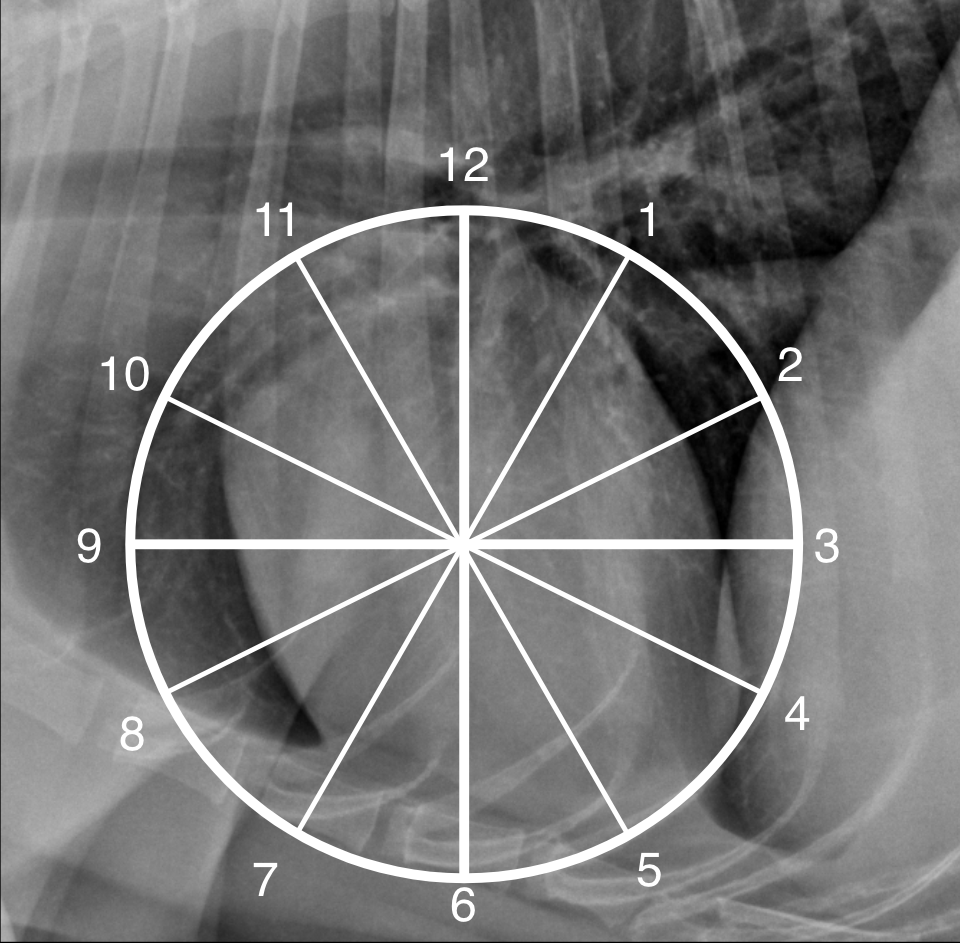

Describe the cardiovascular structures using the “clock analogy” in lateral recumberncy.

A

Clock face analogy to identifying the location of the cardiac chambers

_Lateral view:_ * **12-2 o'clock:** left atrium * **2-5 o'clock:** left ventricle * **5-9 o'clock:** right ventricle * **9-10 o'clock:** main pulmonary artery and right auricular appendage * **10-11 o'clock:** aortic arch _Dorsoventral view:_ * **11-1 o'clock:** aortic arch * **1-2 o'clock:** main pulmonary artery (left auricular appendage in cat) * **2.30-3 o'clock:** left auricular appendage * **2-5 o'clock:** left ventricle * **5-9 o'clock:** right ventricle * **9-11 o'clock:** right atrium _Species differences:_ * On a VD/DV view the cardiac apex points more to the left in the dog. In the cat the apex is more variable, but usually closer to the midline. * **In the dog the left auricular appendage (LAu)** is located at **02.30-03.00 o'clock** on the **DV/VD view. In the cat the LA and LAu** are located at **1-2 o'clock** on this view and the main pulmonary artery may be cranial to this or not seen at all. * In the cat the more cranial location of the LA may make it difficult to see on the lateral view. * **In the dog, when the LA is enlarged** on the **DV/VD view** is superimposed over the cardiac silhouette in the **5-7 o'clock position** (between the caudal mainstem bronchi), whereas in the **cat, it is located more cranially at the 1-2 o'clock position**. This explains the so-called 'valentine heart shape' seen only in the cat and created by left ± right atrial enlargement.